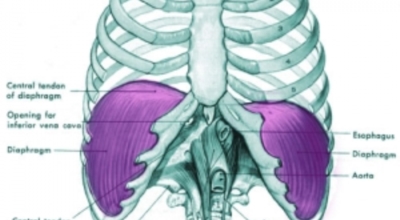

왼쪽 갈비뼈 아래 통증 원인

왼쪽 갈비뼈 아래 통증 - 흉막염

흉막염은 익숙치 않은 병명인데요, 폐를 덮고있는 조직에 염증이 발생하는 질환을 말해요. 흉막염은 대개 폐의 혈전과 연관된 박테리아, 바이러스 또는 진균성 폐렴, 악성 종양, 외상 또는 폐경색의 결과로 일어날 수 있답니다. 왼쪽 흉막염은 왼쪽 흉곽 아래쪽에 통증을 나타나게 할 수 있지만 이것의 주요 증상은 숨을 쉴 때 날카 롭고 찌르는듯한 통증입니다. 호흡 중에 심한 흉통이 있으면 병원에 방문하여 진료를 받아야 해요.